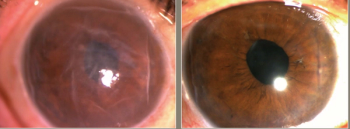

Results from Aurion Biotech's IOTA trial reveals that a corneal endothelial cell therapy showed improvements in visual acuity and central corneal thickness, according to a team of Japanese investigators.